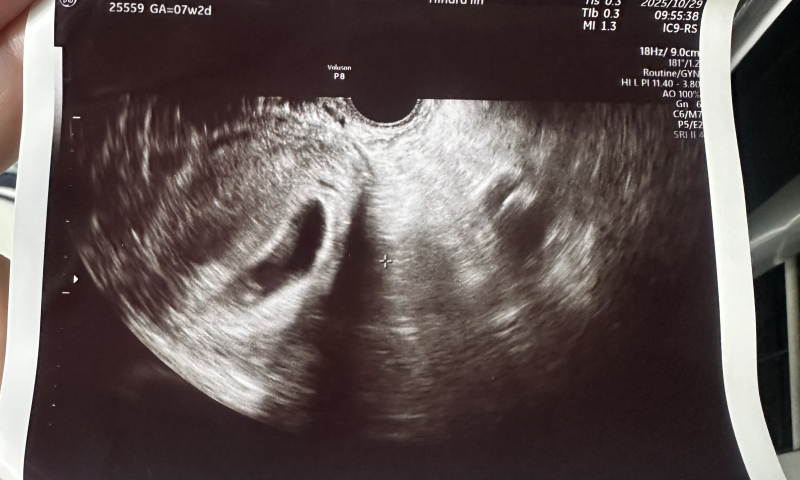

7w2d

「出血も痛みもなく、順調に育ってはいるけどまだ小さめかもしれないので1週間様子を見ましょう」

となりました。

胎嚢が前回の診察時より楕円形になっていること

小さめと言われたことが気になって不安です。